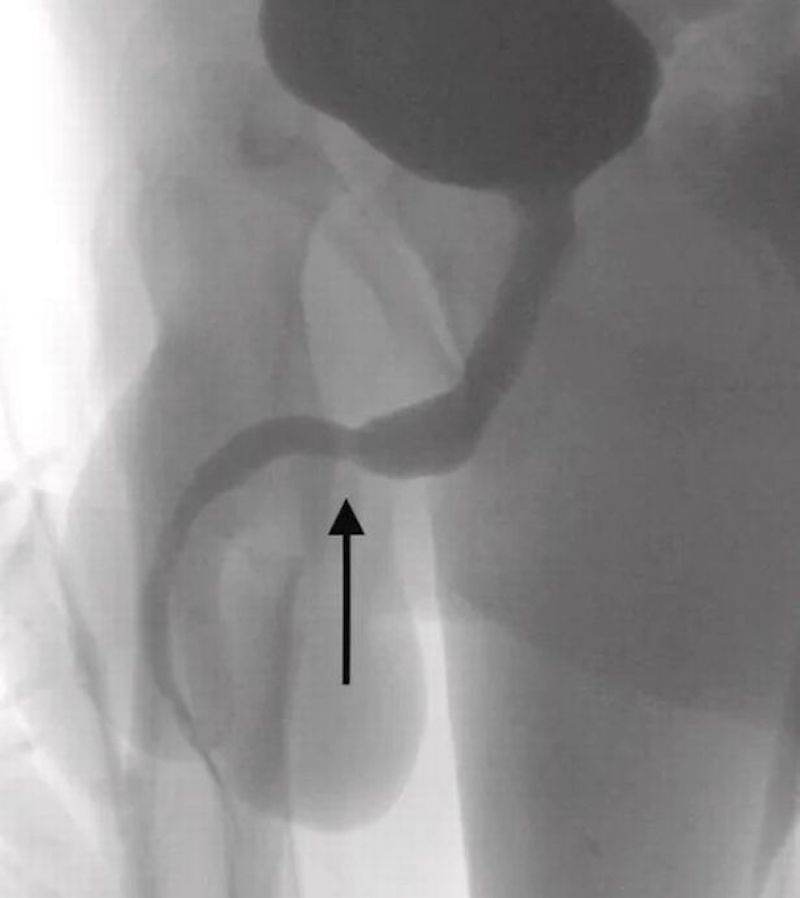

Bagaimanapun, perbuatan anehnya itu telah menyebabkan wayar USB tersebut telah tersangkut dan tersimpul di dalam kemaluannya yang menyebabkan dia perlu dikejarkan ke hospital untuk mendapatkan rawatan.

Lebih ngeri dan ngilu, sebatang besi turut digunakan tetapi tidak berjaya dan akhirnya dia terpaksa memotong bahagian antara kemaluan dan dubur untuk mengeluarkan wayar berkenaan.